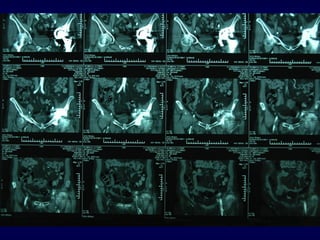

-Rx (segni precoci e tardivi)

-Scintigrafia (Tc – Leucociti marcati)

-Angiografia – Angio-TAC (2D – 3D)